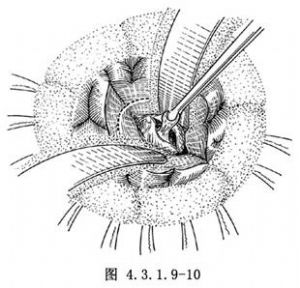

較大腫瘤,活動度小且較難遊離者,不應強行完整切除。應先行包膜內或囊內分塊切除(圖4.3.1.9-10)。再在顯微鏡下電凝包膜表面血管,遊離腫瘤基底,電凝和夾閉血管後將腫瘤全部切除。對血供豐富的腫瘤有條件單位可採用微波熱凝、激光氣化或超聲吸引等方法進行切除。